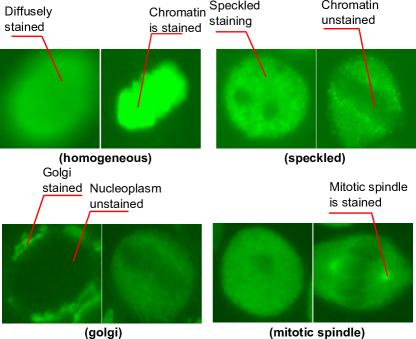

Contributions The aim of the present work is to devise an algorithm which learns image descriptors for ANA IIF specimen image classification problem with three properties: (1) highly discriminative; (2) semantically meaningful at cell level and (3) having short descriptor length. We achieve this by proposing two learning schemes for discovering cell-level attributes through a discriminative learning framework. In contrast to previous approaches [1, 16] which learns discriminative image-level attributes, our approach learns cell-level attributes where their values can be used to construct discriminative image-level descriptors. Our theoretical results show that under a certain condition, it is possible to devise solutions based on image-level discriminative attribute learning for solving the posed problem. Finally, we further showcase (refer to Fig. 1 for some examples of discovered meaningful cell attributes) that a textual description can be generated from the learned cell-level attributes and shares similarities to the description from experts. We evaluated all the approaches on the new HEp-2 cell dataset proposed for the specimen image classification problem. To our knowledge this is the first comprehensive dataset constructed for this purpose.

We first selected the most frequently appearing cell-level attributes from each pattern. From the selected set, we further excluded the attributes which appear in at least more than four classes. Finally, to name the cell attributes, we presented each cell attribute to the domain experts who were trained to read ANA by showing them both images classified as positive and negative by the attribute classifier. We note that we presented the cell images in green colour which is similar to the colour of an ANA specimen under a fluorescent microscope. Since the attributes are extracted from each cell region, we could ask more specific questions to the experts in relation to each region (e.g. Please describe the property appearing at the cell boundary). The experts could opt not to name an attribute if they were not able to find any consistent property in the positive cell images. Fig. 5 and 1 present some examples of cell attributes successfully identified by the experts.

Once the description for each class was generated, we let the experts indicate the correctness of each text description. Fig. 6 presents the generated description of each pattern. Most patterns could be reasonably described with minor errors or omissions in the description. The mitotic spindle pattern was perfectly described with no errors or omissions in the description. On the other hand, despite this system being able to detect the important property of Golgi (i.e. golgi organelle is stained), the system had more mistakes on Golgi than the other patterns. This is probably due to the fact that the Golgi pattern has only one prominent property.